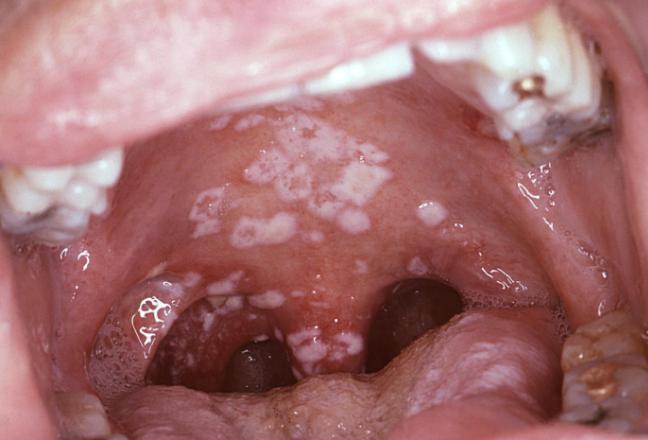

アフタ性口内炎・難治性口内炎 - 熊本 くまモンファン 耳鼻咽喉科医の みみ・はな・のど あれこれ。